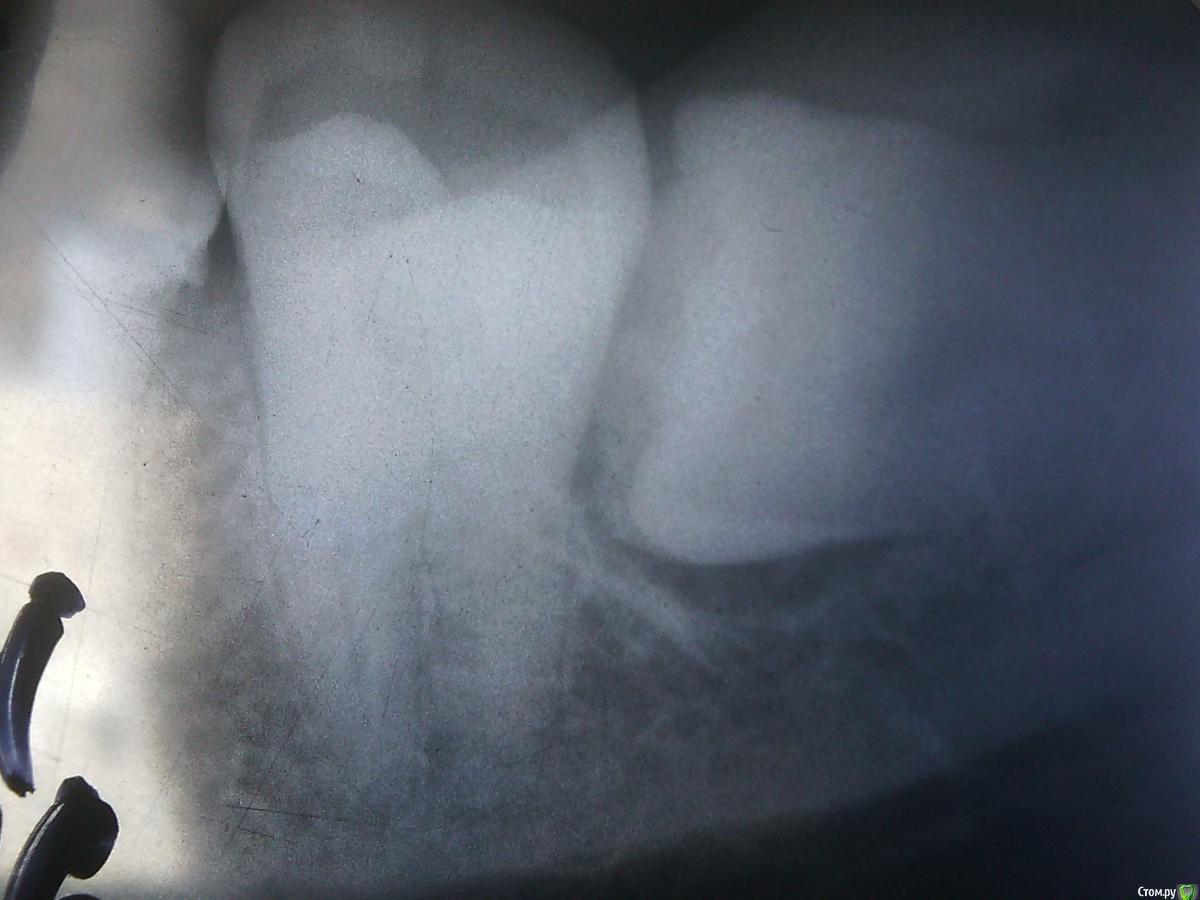

diesel87 Опубликовано 19 февраля, 2016 Поделиться Опубликовано 19 февраля, 2016 Виталий, я вот как-то удалял зубик почти как тот, что удалил ты. только корень был толстенный и назад еще длиннее шел за коронку на ширину коронки. результат ущимление пучка и парестезия на пол года((... жаль только фото не сделал, а коллега его выбросила...А как удалял то? Зуб распиливал? Посмотрел кстати пациентку через неделю, все хорошо и сделал снимок после, так как много желающих было увидеть раскуроченную лунку) Ссылка на комментарий

Аслан Опубликовано 22 февраля, 2016 Поделиться Опубликовано 22 февраля, 2016 А как удалял то? Зуб распиливал? в том-то идело что нет, просто вывихнул дистально.у меня остался только прицельный снимок ееhttp://s019.radikal.ru/i600/1602/43/cb1809042bc9.pngи кусочек орто через год после удаленияhttp://s019.radikal.ru/i628/1602/bb/10112bf1098c.png 1 Ссылка на комментарий